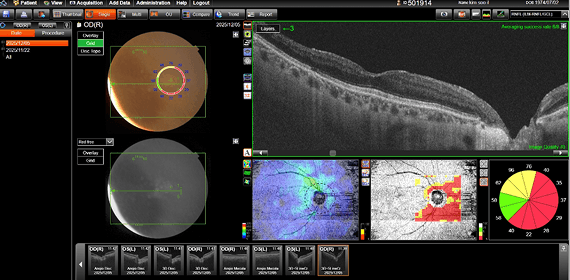

수술 전후의 객관적인 검사 결과를 통해

강남도쿄안과의 정교한 진료를 직접 확인해 보세요.